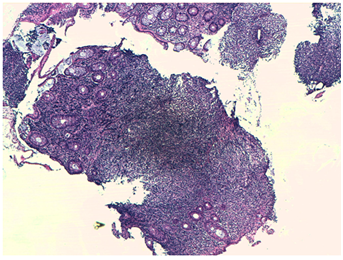

We consulted with the Surgery team and exeresis of the larger inguinal lymphadenopathy was carried out for anatomopathological study.

Finally, after histopathological and immunohistochemical study, the diagnosis of follicular non-Hodkin B lymphoma, histological grade 2, was confirmed in both anatomopathological samples.

Figure 4 Follicular pattern in inguinal adenopathy. Tumor composed of atypical large lymphoid cells with pleomorphic nuclei and prominent nucleolus

Figure 5 Follicular pattern in colon sample.